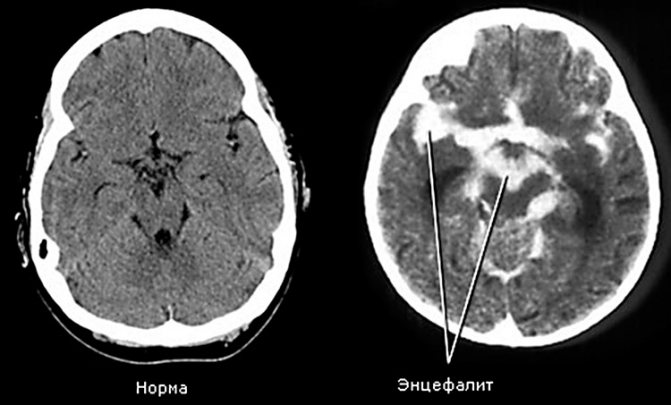

Энцефалит может быть предупрежден при своевременной диагностике.

Когда человека укусила бешеная кошка, даже если она не отличается от здоровой и выглядит вполне нормально, лучше не рисковать здоровьем и жизнью, и как можно скорее обратиться за помощью. Инфекцию не удается распознать с помощью диагностических методов, однако можно исключить другие патологии с похожей симптоматикой. К таким относятся:

- энцефалит;